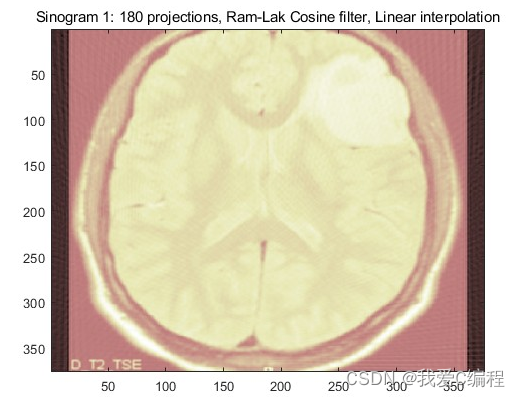

4.内容简介

直接由正弦图得到反投影图像,会存在严重的模糊,这是早期 CT 系统所存在的问题。傅立叶中心切片定理表明,投影的一维傅立叶变换是得到投影区域的二维傅立叶变换的切片。滤波反投影重建算法在反投影前将每一个采集投影角度下的投影进行卷积处理,从而改善点扩散函数引起的形状伪影,有效地改善了重建的图像质量。